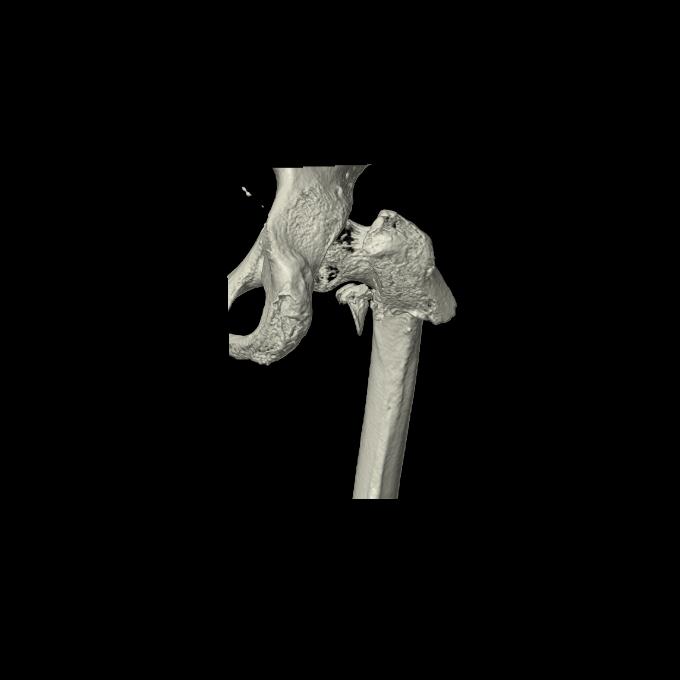

110286 2/17 股関節 2R 74歳女性 右人工骨頭

102903 股関節 2R 1/28 +股関節 2R 1/29 78歳女性 左人工骨頭

82084 1/14 1/20 股関節 2R 78歳男性 右人工骨頭

91569 3/25 両股正面とラウエン 70歳女性 人工骨頭+バンクーバー